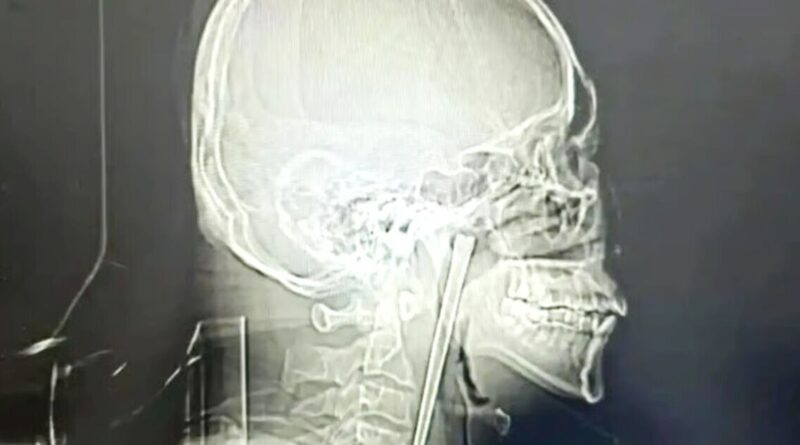

This is the incredible X-ray of a man in China showing a 12cm-long chopstick he had stuck in his throat for an astounding eight years, because he was terrified of surgery. The man, who it’s reported had the surname Wang, only eventually went to hospital in March after finally having enough of the oesophageal interloper.

Eventually however Mr Wang decided to undergo surgery and had the chopstick removed at Dalian Municipal Central Hospital in northeastern Liaoning province in early March. X-rays of the chopstick show how he endured having the huge eating implement lodged in his neck for nearly a decade.